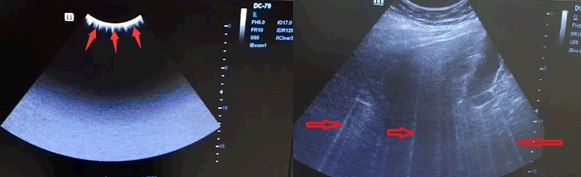

⚠️ Проблема: При включенной гармонике в области изображения иногда могут «мигать» белые линии. Они могут исчезнуть при включении и выключении "сток-кадр". На рисунках ниже показан пример.

💡 Причина: Программируемая логическая матрица TR-FPGA на плате TR64 вышла из строя, что приводит к сбою. Сбой происходит только при включенной гармонике. Вы можете попробовать выключить гармонику, чтобы понять, остается ли проблема после выключения гармоники.

✅ Решение: Программируемая логическая матрица TR-FPGA на плате TR64 в аппарате Mindray DC-70 была изменена на ECN (EGD019F). При столкновении с такой проблемой на DC-70, обновите программное обеспечение Doppler до версии V01 08 01 или выше.